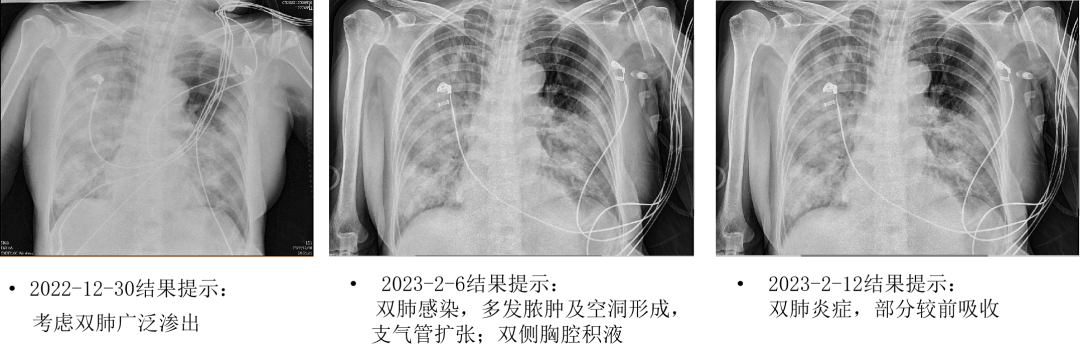

2022-12-30胸片:考虑双肺广泛渗出,主动脉粥样硬化

2023-2-8胸部CT:(见图1、图2)

• 考虑双肺感染,多发脓肿及空洞形成,支气管扩张。

• 对比2023-01-30胸部CT,部分空洞较前稍缩小,余大致同前

2023-2-12胸片